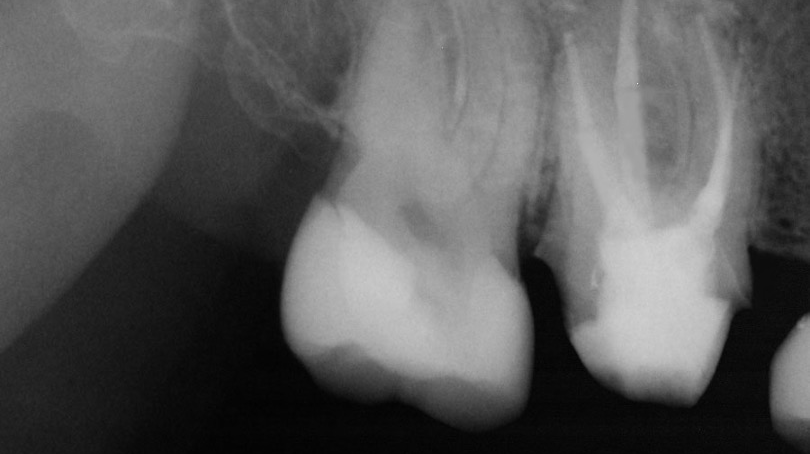

Figure 1 from Endodontic Periapical Lesion An Overview on the Etiology What Is Endodontic Posts The purpose of an endodontic post is to help restore or reinforce the coronal structure of a tooth, further increasing the retention and stability of an. The susceptibility of endodontically treated teeth (ett) to fracture has long been a concern in dentistry. An endopost, dental post or pin, is a rigid structure a few millimeters long, which is placed in. What Is Endodontic Posts.